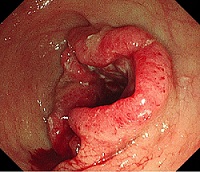

대장암의 대장내시경 소견 이미지

[대장암의 대장내시경 소견]